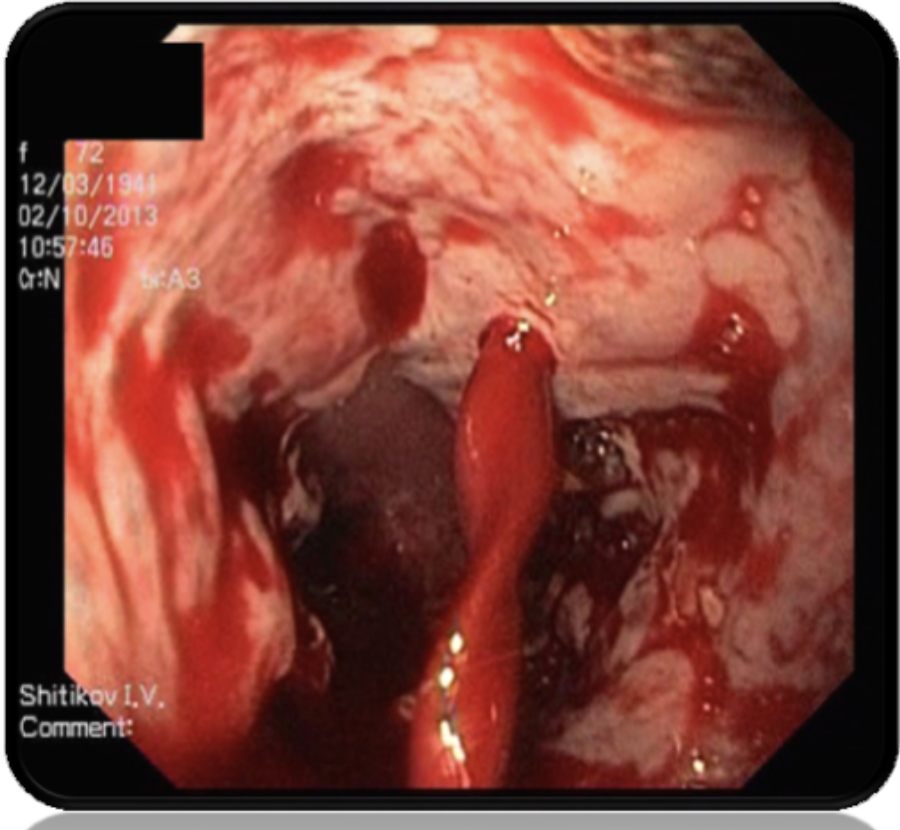

Сегодня стандартом в лечении острого пищеводно-желудочного кровотечения на начальном этапе является местная эндоскопическая терапия в виде лигирования в сочетании с вазоактивными препаратами, направленная на эрадикацию варикозных вен. Однако, не смотря на применение современных «золотых стандартов» фармакологической и эндоскопической терапии, у 15 - 20% пациентов портальной гипертензией первичное массивное кровотечение исключает возможность эндоскопического лигирования, либо в течение ближайших пяти суток наступает его рецидив. Летальность у таких пациентов достигает 30 - 50%.

Исследования последних лет свидетельствуют о том, что при рефрактерном варикозном пищеводном кровотечении средством гемостаза столь же эффективным и более безопасным, чем баллонная тампонада зондом-обтуратором Sengstaken – Blakemore, могут быть пищеводные саморасширяющиеся нитиноловые стенты Danis. Однако, не смотря на рекомендации, выработанные в ходе целого ряда консенсусных встреч, эта позиция в лечебной программе варикозного кровотечения остается до конца не решенной (рис. 2).

Проанализированы результаты лечения варикозного кровотечения из пищевода, рефрактерного к медикаментозной и эндоскопической терапии у 59 больных внутрипеченочной портальной гипертензией (рис. 3).

Механический гемостаз в группе сравнения был достигнут в 33 (75,0%) клинических наблюдениях. В то же время у 11 (25,0%) пациентов наступил рецидив, в том числе у 9 (20,5%) сразу же после распускания баллонов, у 2 (4,5%) – после удаления зонда – обтуратора. В основной группе гемостаз был достигнут в 13 (86,7%) клинических наблюдениях. В то же время у 2 (13,3%) пациентов остановить кровотечение с помощью стента не удалось. Произошла дистальная миграция стента с потерей его тампонирующей функции (рис. 6).